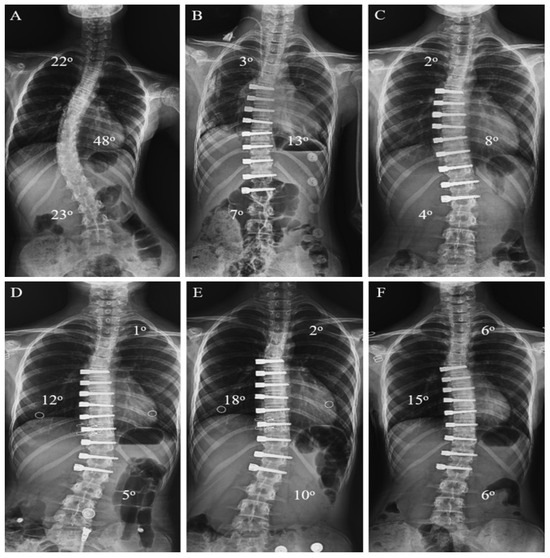

Background/Objective: The anterior vertebral body tethering (AVBT) technique, which preserves spinal mobility and avoids possible fusion problems in adolescent idiopathic scoliosis (AIS) patients, continues to be increasingly used in spine surgery. The study aims to report the early-to-early-mid postoperative radiological results of thoracolumbar/lumbar AVBT on sagittal alignment, and the second aim is to compare AVBT with selective thoracic fusion (STF) and non-selective fusion (NSF) groups in AIS patients. Methods: Patients with a diagnosis of AIS were retrospectively evaluated in the study. All patients were categorized into three groups based on the surgical technique performed: AVBT (n = 17), NSF (n = 19), and STF (n = 15). The major curvature degree, coracoid height difference (CHD), sacral slope (SS), pelvic tilt (PT), pelvic incidence (PI), lumbar lordosis (LL), thoracic kyphosis (TK), cervical lordosis (CL), C7 tilt, sagittal vertical axis (SVA), T1 pelvic angle (TPA), and T1 spinopelvic inclination (T1SPI) were measured for radiological comparison. Scoliosis Research Society-22 (SRS-22) and Oswestry Disability Index (ODI) scores were used at the final follow-up for functional evaluation. Results: The T1SPI value of the NSF group was significantly higher than the STF group in the final follow-up (p = 0.033). The mean decrease of 8.85 ± 7.85 units in the final follow-up value compared to the postoperative CHD value of the patients in the AVBT group was found to be significant (p = 0.028). Statistically significant differences were found between preoperative and the first postoperative CL and TPA measurements (p = 0.001 and p = 0.042, respectively), as well as between preoperative and final follow-up CL measurements in the AVBT group (p = 0.001). No statistically significant differences were observed between the groups in CHD, SS, PT, PI, LL, TK, CL, C7 tilt, SVA, and TPA values (p > 0.05); similarly, the SRS-22 and ODI scores did not differ significantly among the groups (p > 0.05). Conclusions: Thoracolumbar/lumbar AVBT surgery led to significant improvements in shoulder asymmetry and cervical lordosis of AIS patients in the early to early-mid postoperative period. However, compared with spinal fusion techniques, thoracolumbar/lumbar AVBT did not demonstrate superiority in functional scores or sagittal parameters. The mid- to long-term benefits of thoracolumbar/lumbar AVBT remain uncertain and require further investigation. Full article

Figure 1